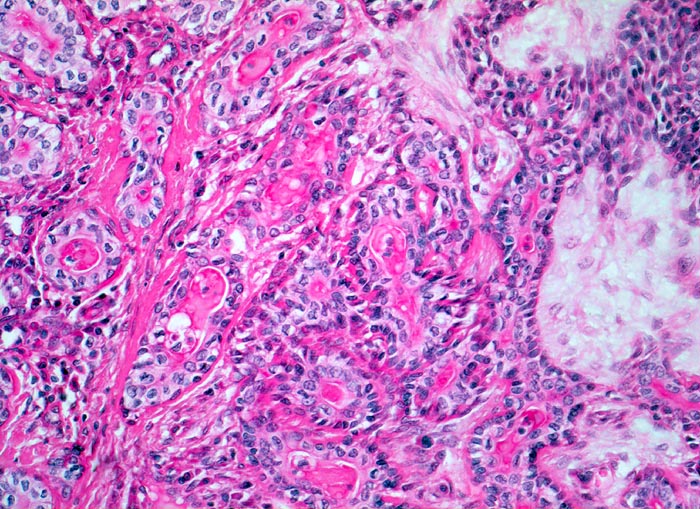

Mikroskopie und Histogenese:

Die architektonischen und zytologischen Befunde sind äusserst variabel. Pleomorphe Adenome bestehen aus einer duktalen epithelialen, einer myoepithelialen und einer mesenchymalen Komponente mit myxoider, hyaliner, chondroider oder ossärer Differenzierung. Der Prozentuale Anteil der verschiedenen Komponenten ist von Tumor zu Tumor sehr unterschiedlich. Gangstrukturen werden von einem einreihigen duktalen Epithel ausgekleidet. Das Gangepithel kann eine Plattenepithelmetaplasie mit Verhornung zeigen. Die Myoepithelzellen umgeben die epithelial ausgekleideten Gangstrukturen, bilden Nester, solide Zellplatten, Trabekel oder liegen einzeln im mesenchymalen Stroma. Die Morphologie der Myoepithelien ist sehr variabel (spindelig, plasmazytoid, epitheloid, sternförmig oder basaloid).

• Scharf begrenzter bekapselter Tumor bestehend aus epithelialen, myoepithelialen und mesenchymalen Anteilen.

• Das Epithel bildet duktale Strukturen, welche von reichlich Myoepithelien umgeben werden.

• Epitheiale Gänge werden ausgekleidet von kubischen luminalen Zellen und einer oder mehreren äusseren Schichten myoepithelialer Zellen.

• In den stromareichen Arealen rechts finden sich plasmazytoide Myoepithelzellen mit reichlich eosinophilem Zytoplasma und einem exzentrisch gelegenen runden Kern.

• Die stromale Komponente ist teils mukoid, teils hyalinknorplig, teils hyalinisiert bindegewebig.